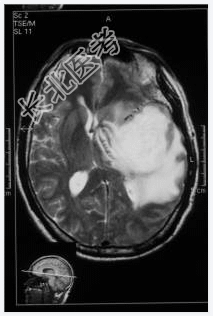

- [材料题] 患者,男性,58岁,因头疼1月余,伴嗜睡、记忆力下降、性格改变1周入院。头颅MRI检查。

- 简答题1、诊断及依据是什么?

- 简答题2、鉴别诊断有哪些?